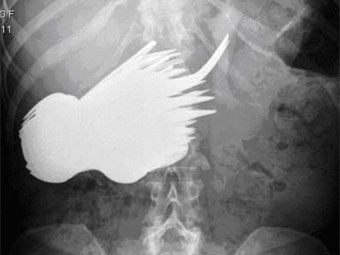

Рентгеновский снимок брюшной полости Маргарет Даалман с сайта dailymail.co.uk

Жительница Голландии проглотила 78 столовых приборов. Об этом 29 октября пишет газета The Daily Telegraph.

52-летняя Маргарет Даалман, работающая секретарем в одном из роттердамских агентств недвижимости, попала в больницу с жалобами на боли в животе. Рентгеновское обследование показало, что в ее пищеварительном тракте находится множество посторонних предметов.

В ходе экстренной операции из живота Даалман извлекли 78 серебряных ложек и вилок. Позднее она сообщила врачам, что "захотела поесть серебра и не могла удержаться". Выяснилось, что раньше женщина уже была замечена за поеданием столовых приборов, но не в таких больших количествах.